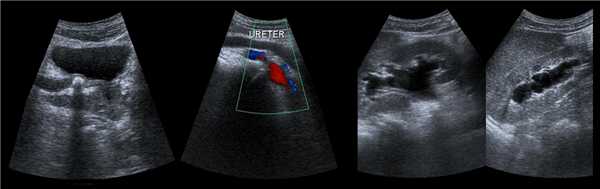

Рисунок. У новорожденного на УЗИ почек определяется гидронефроз (1) и расширенный мочеточник (2) справа. В мочевом пузыре двустороннее уретероцеле (3). При исследовании левой почки структурных изменений не выявлено.

Рисунок. На УЗИ расширенный дистальный отдел мочеточника (1, 2, 3). Про уретероцеле (3) подробнее смотри здесь.